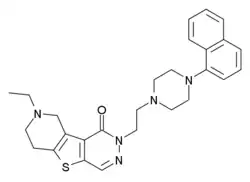

- Another ligand that has been recently disclosed is shown below, claimed be a selective 5-HT5A agonist with Ki = 124 nM.[21]

- ^ US 6750221, Garcia-Ladona FJ, Szabo L, Steiner G, Hofmann HP, "Use of 5-HT5-ligands in the treatment of neurodegenerative and neuropsychiatric disturbances", published 2004-06-15